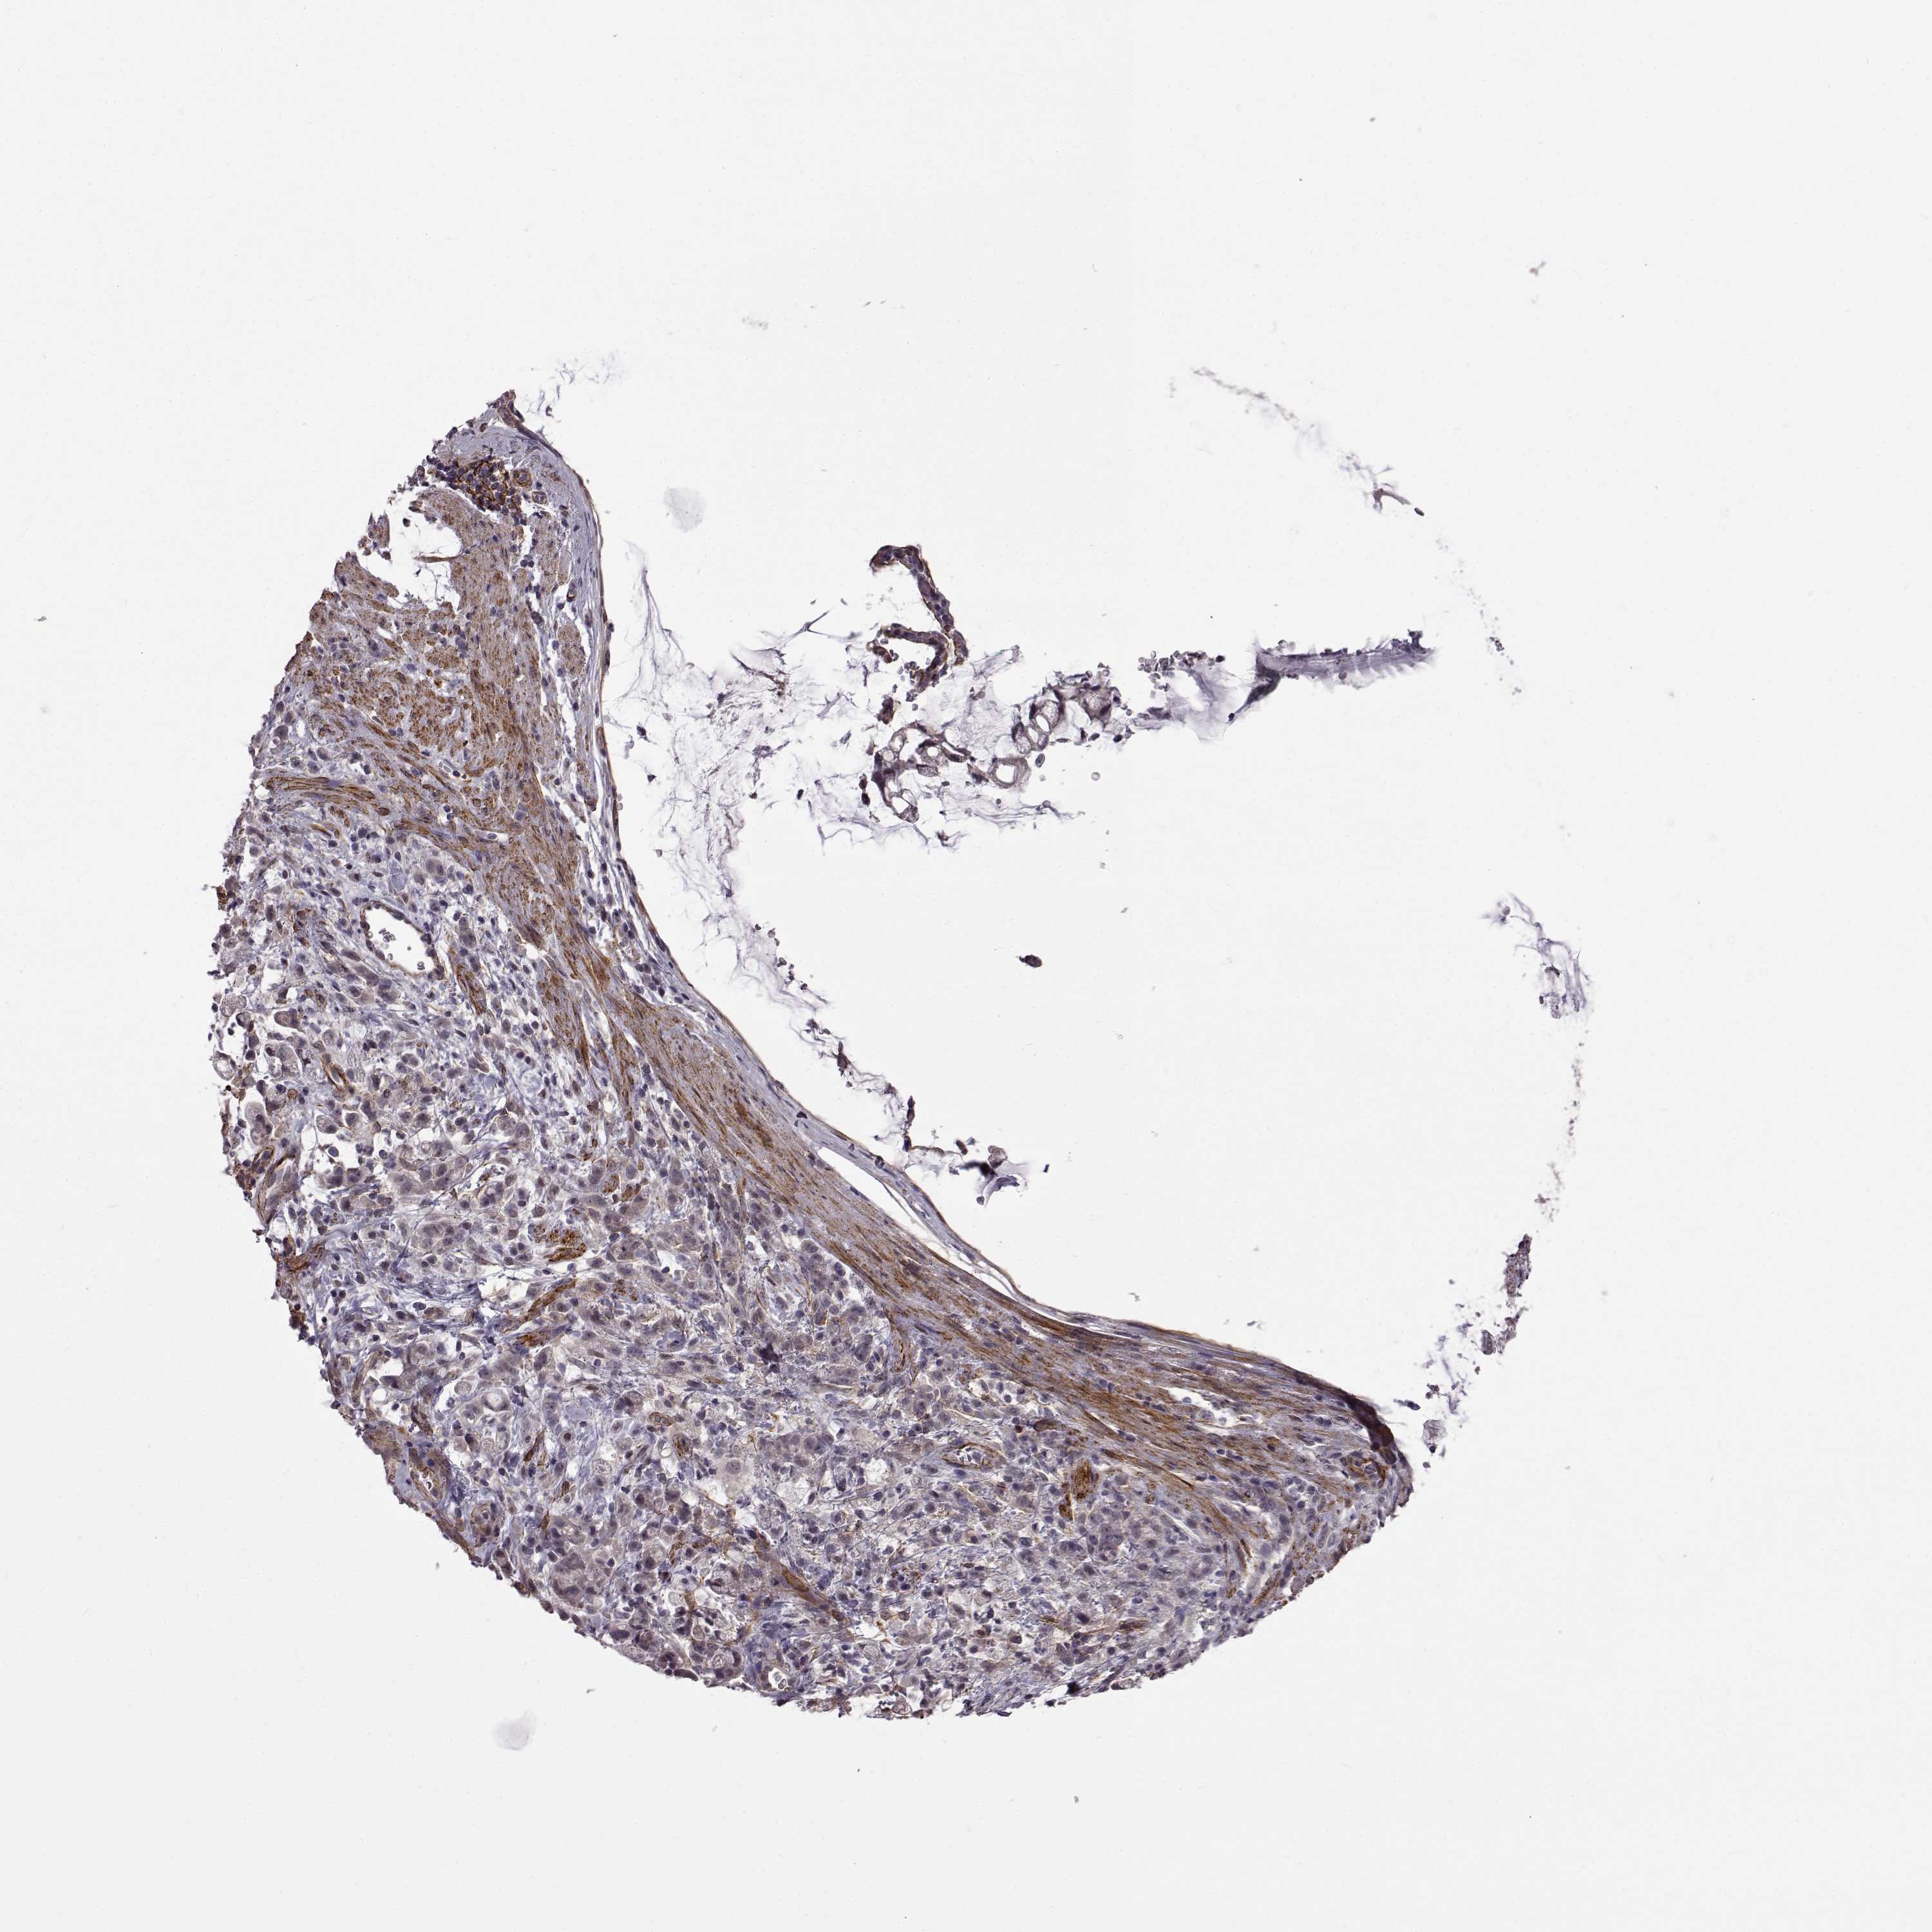

STOMACH CANCER - Protein expressioni

A mouse-over function shows sample information and annotation data. Click on an image to view it in a full screen mode. Samples can be filtered based on level of antibody staining by selecting one or several of the following categories: high, medium, low and not detected. The assay and annotation is described here.

Antibody stainingi

Antibody staining in the annotated cell types in the current human tissue is reported as not detected, low, medium, or high, based on conventional immunohistochemistry profiling in selected tissues. This score is based on the combination of the staining intensity and fraction of stained cells.

Each image is clickable and will lead to virtual microscopy that enables deeper exploration of all samples and also displays staining intensity scores, fraction scores and subcellular localization as well as patient and tissue information for each sample.

Antibody HPA030665

Antibody HPA068563

Antibody CAB037231

Staining

High

Medium

Low

Not detected

Intensity

Strong

Moderate

Weak

Negative

Quantity

>75%

75%-25%

<25%

None

Location

Nuclear

Cytoplasmic/membranous

Cytoplasmic/membranous,nuclear

Adenocarcinoma, NOS